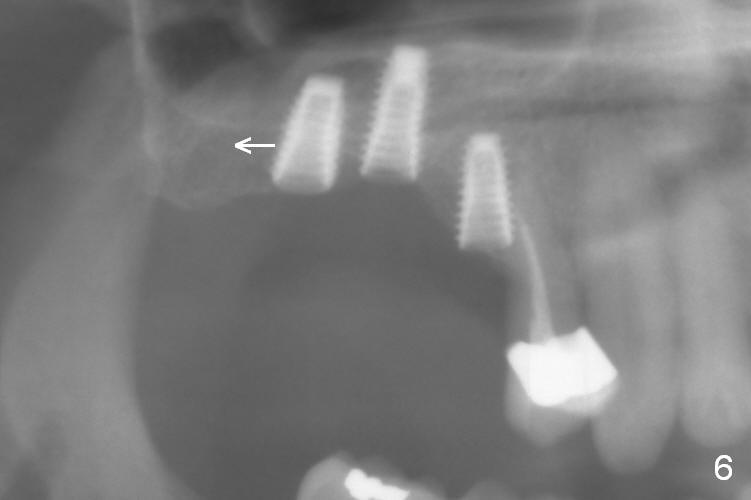

After use of 2.8 mm round bur at #4 for sinus lift, a 4x8.5 mm regular drill is used with resultant sinus membrane perforation at the sinus floor. The latter is repaired with insertion of Osteogen plug prior to place 4.5x8.5 mm implant (Fig.5,6). The similar mistake occurs at #3: after using 2.4/3.7 mm bone expander for 10 mm, a 4x10 mm is used, which also results in sinus perforation, probably sideway, buccally. Trimmed Osteogen plug is placed before a 4.5x10 mm implant is placed with primary stability (Fig.6). The reason for use of the regular drills is to avoid ridge fracture due to under prep.

Since the bone at #2 is soft, the 3.6 mm round drill is used after 2.8 mm one. When a 5x8.5 mm implant is placed, there is no ridge fracture. The implant at #2 should have been placed more distal (Fig.6 arrow).

Insertion torque of the three implants is ~ 50 Ncm. Three long (because of severe vertical bone resorption (Fig.1,6)) abutments are placed immediately for immediate splinted provisional (Fig.7,8 P). The latter should have hemostatic effect. Application of peridontal dressing (D) has additional hemostatic function, exerting pressure the most anterior (Fig.7 between the teeth #5,6) and the most posterior (Fig.8 arrow) incision, where the provisional cannot. Sulcus incision is good to remove subgingival calculus. It seems that chronic periodontits and bruxism play roles in pathogenesis of bone loss.